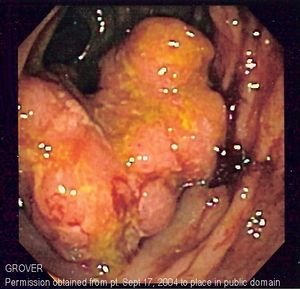

Endoscopic image of colon cancer identified in sigmoid colon on screening colonoscopy in the setting of Crohn's disease.

• تنظير القولون: يستخدم تنظير القولون أنبوبًا طويلاً ومرنًا ورفيعًا يتصل بكاميرا فيديو وشاشة لعرض القولون والمستقيم بأكملهما. إذا تم العثور على أي مناطق مشتبه في إصابتها بالمرض، يمكن للطبيب تمرير الأدوات الجراحية من خلال أنبوب لأخذ عينات من الأنسجة (خزعات) لتحليلها وإزالة السلائل.